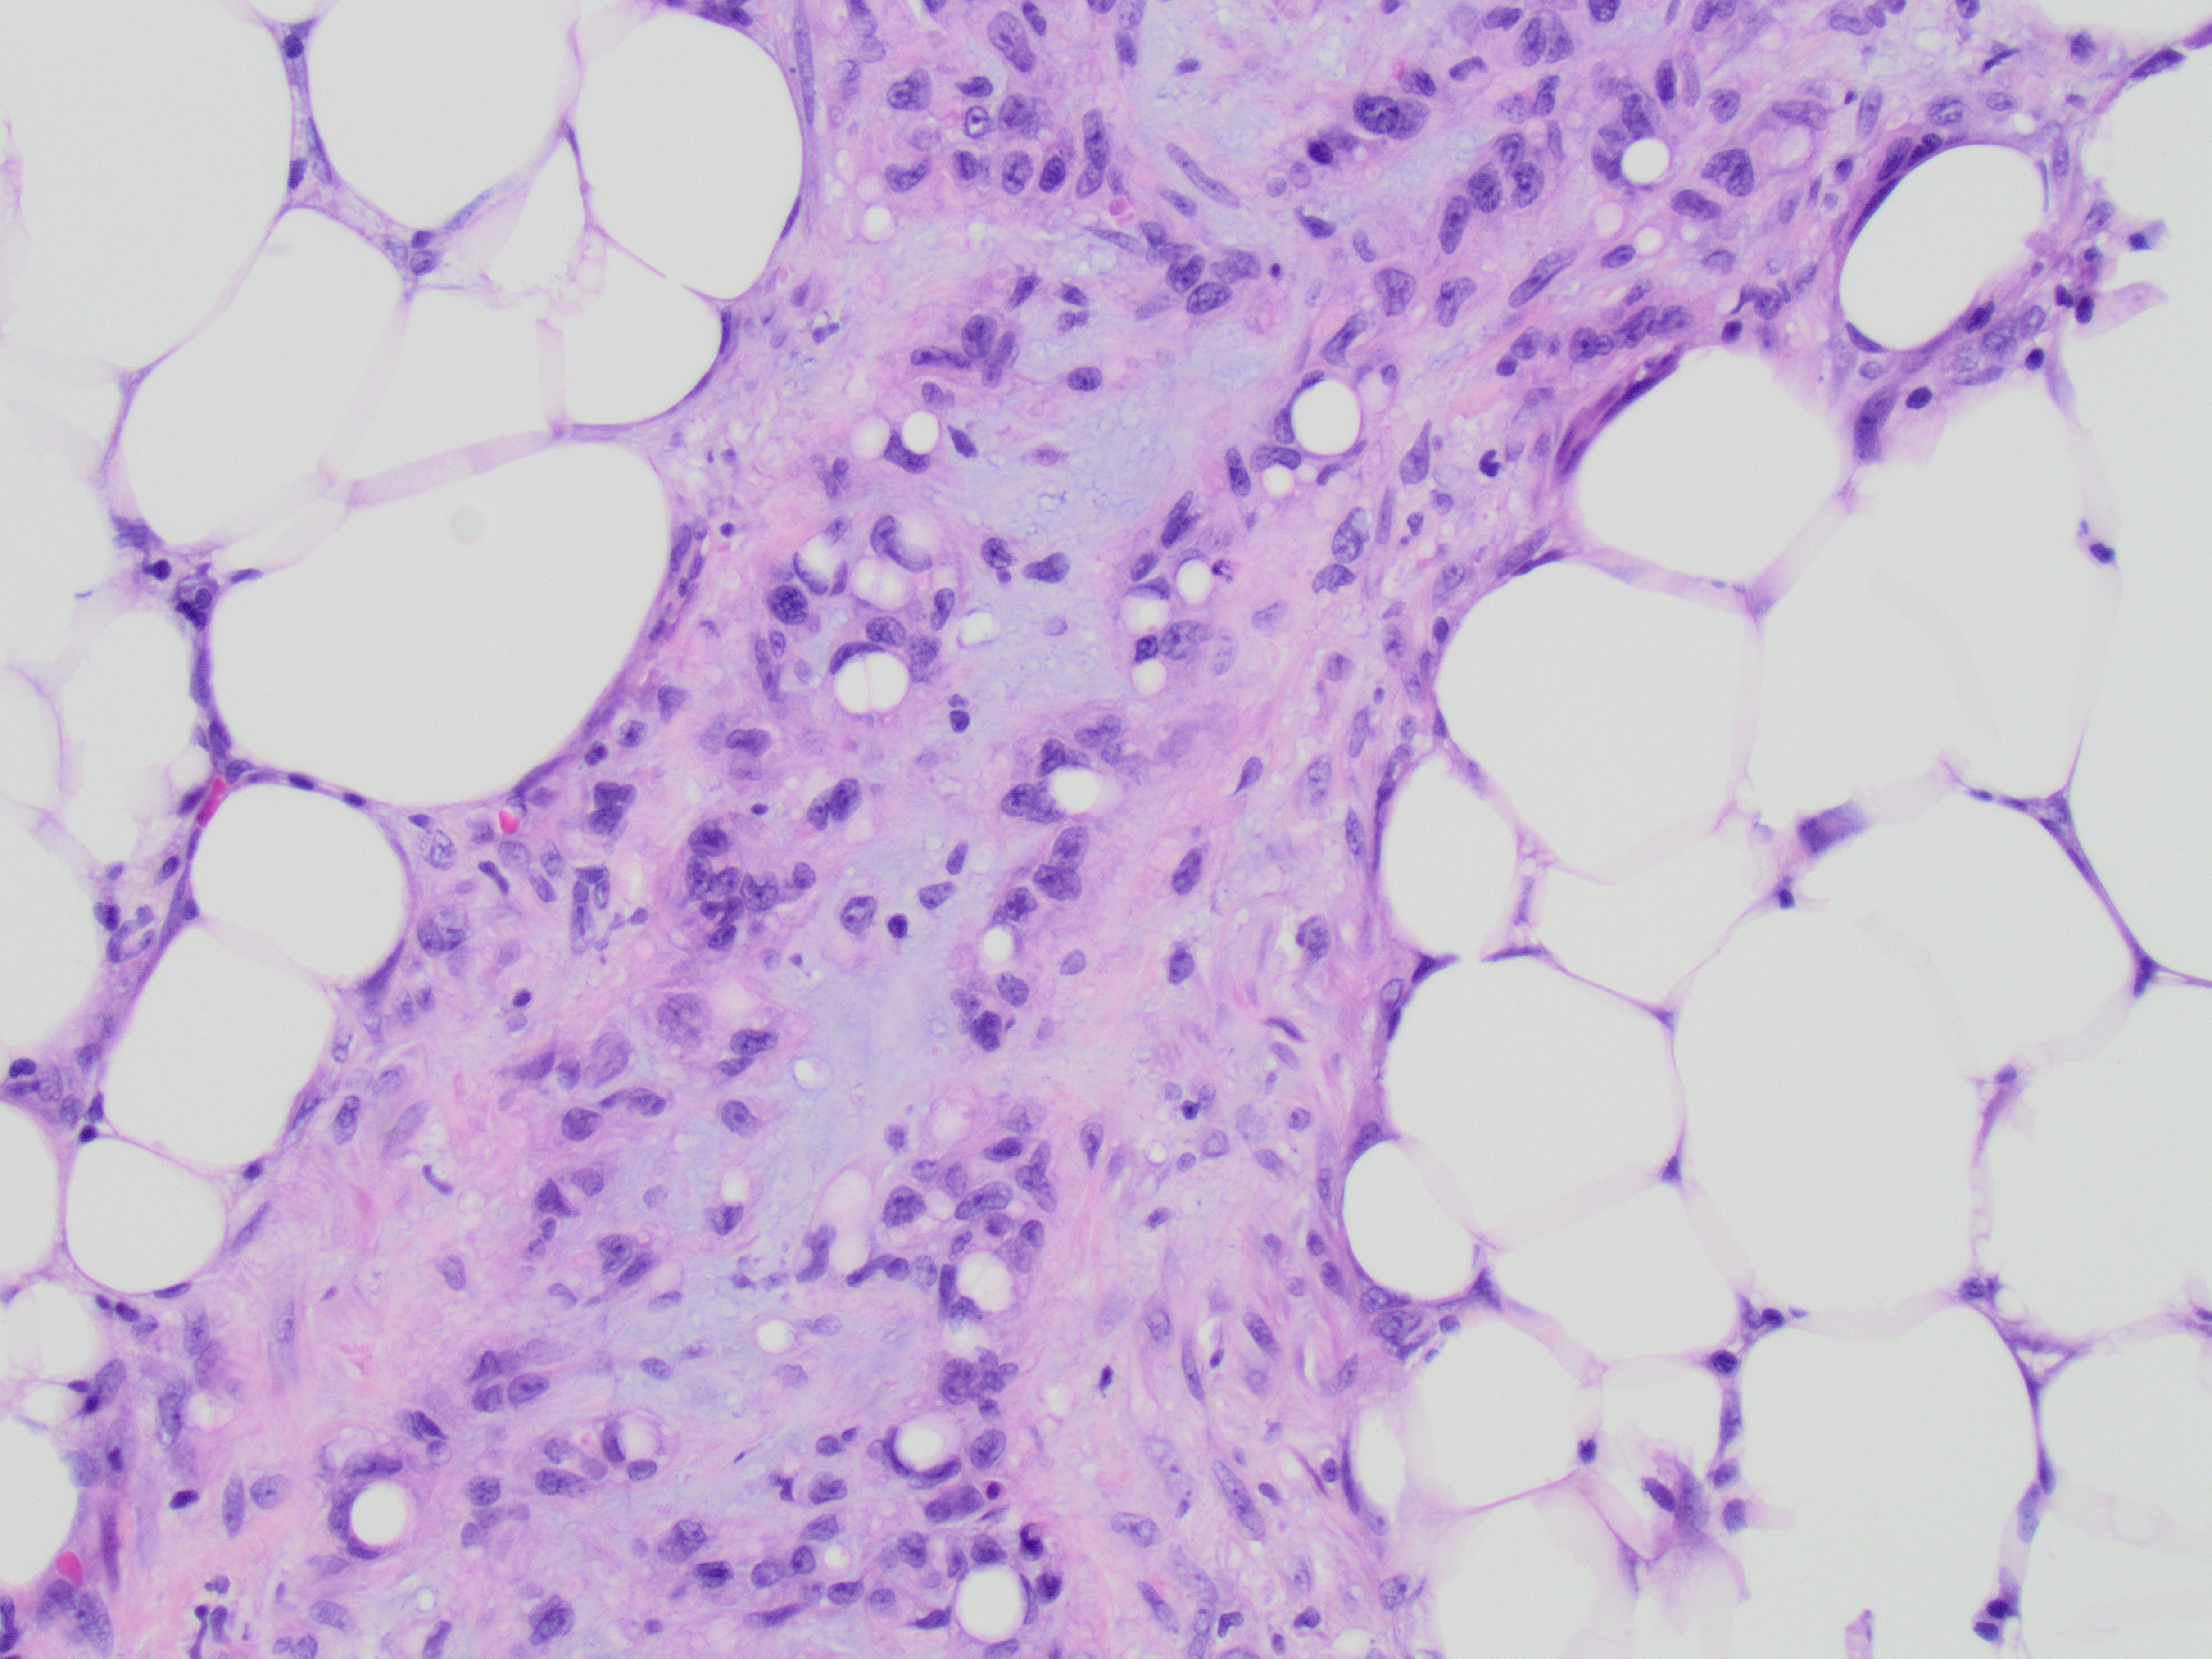

A 45-year old man with a history of PTC, tall cell variant (PT3b N1a M0), s/p total thyroidectomy, central neck lymph node excision and radioactive iodine therapy, presents with new neck mass. Figures a & b show FNA of the mass.